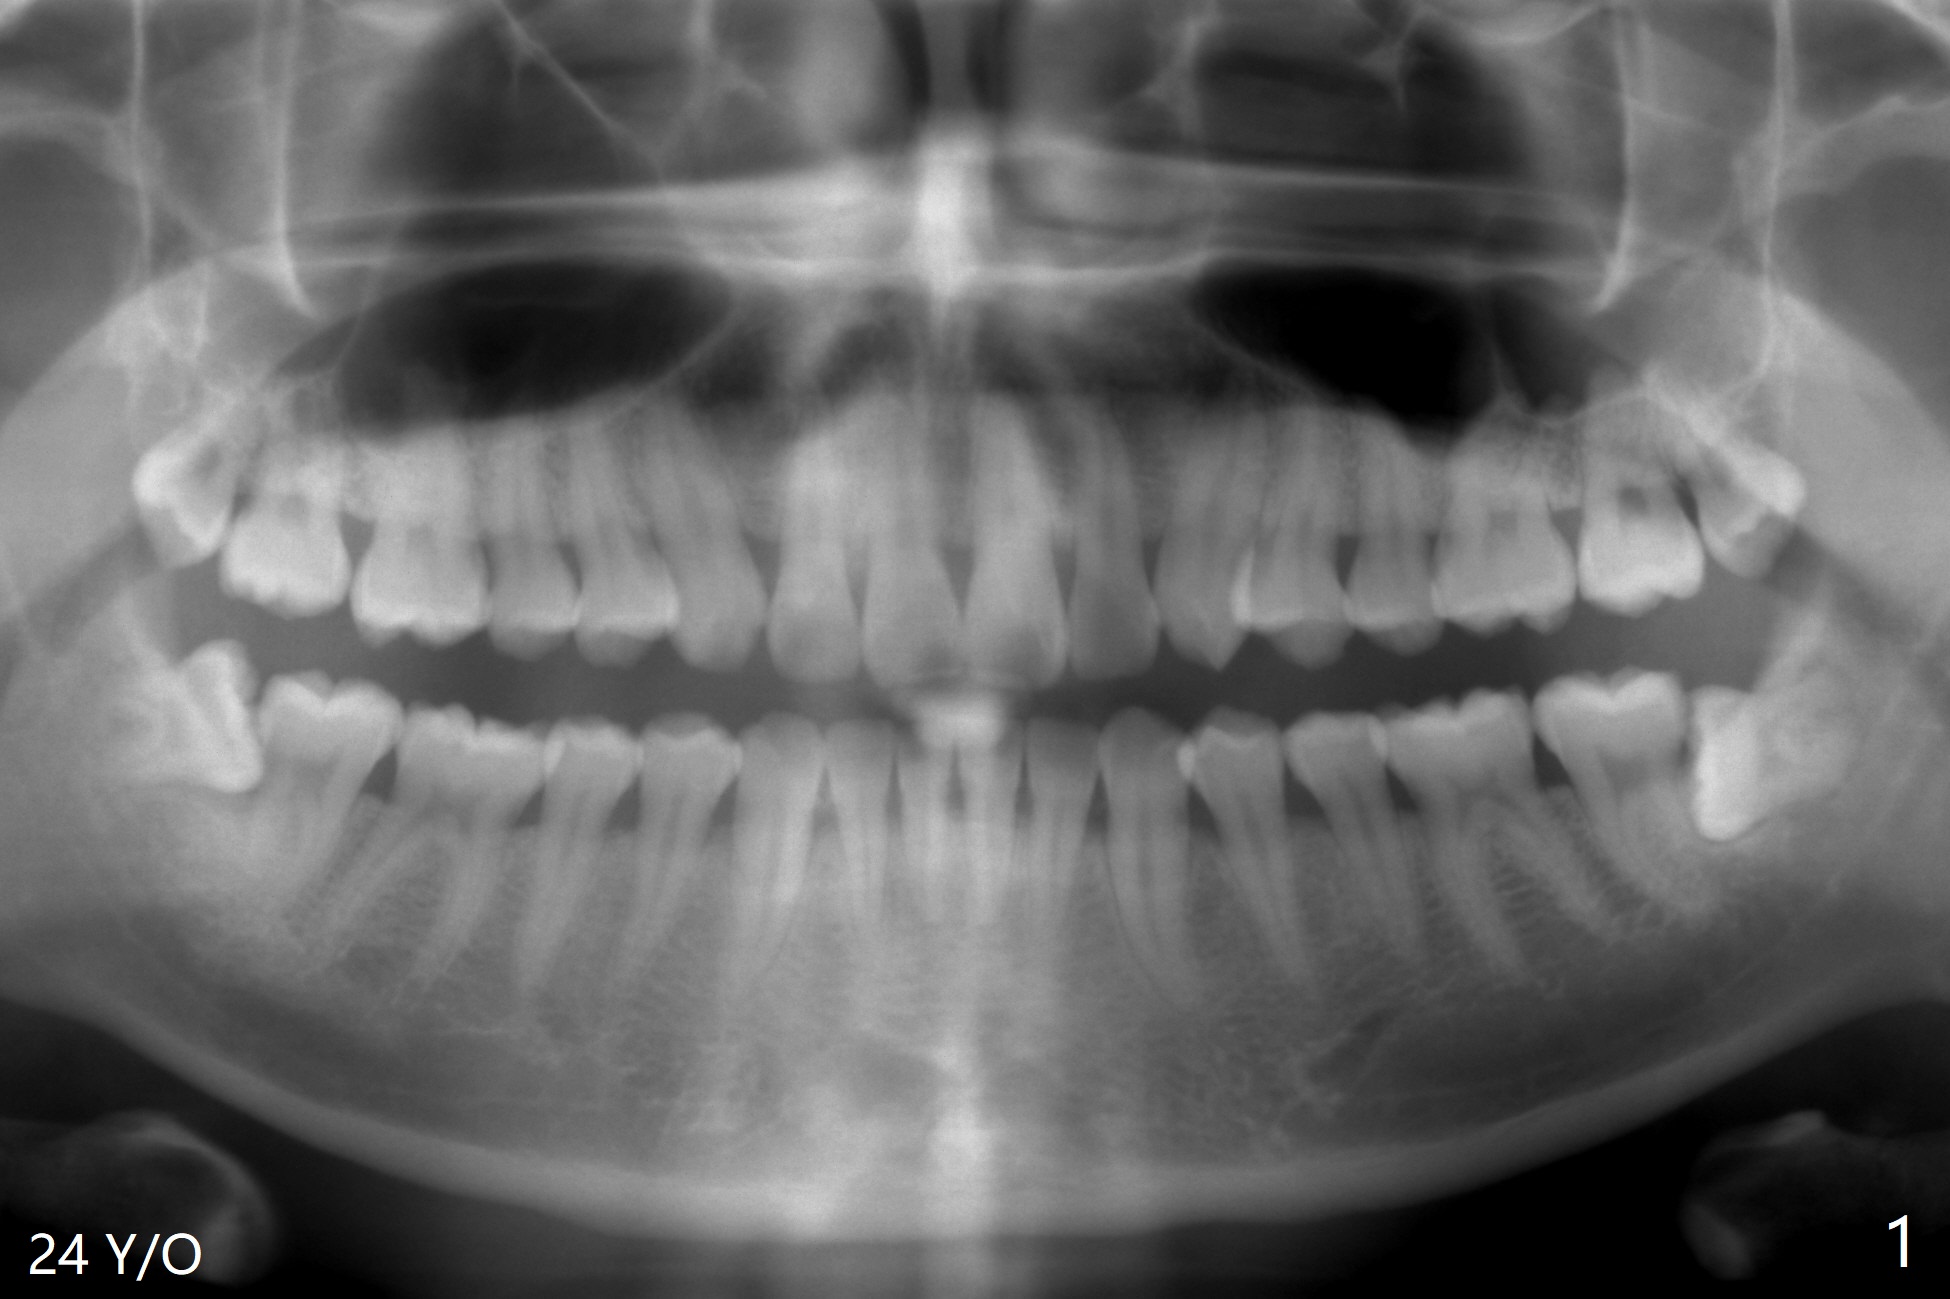

A 24-year-old man presents to clinic for #16, 17 and 32 extraction (Fig.1). Osteogen plug is placed in the last two sockets. All of the 3 sockets heal 4 years later (Fig.2). The tooth #1 is extracted.